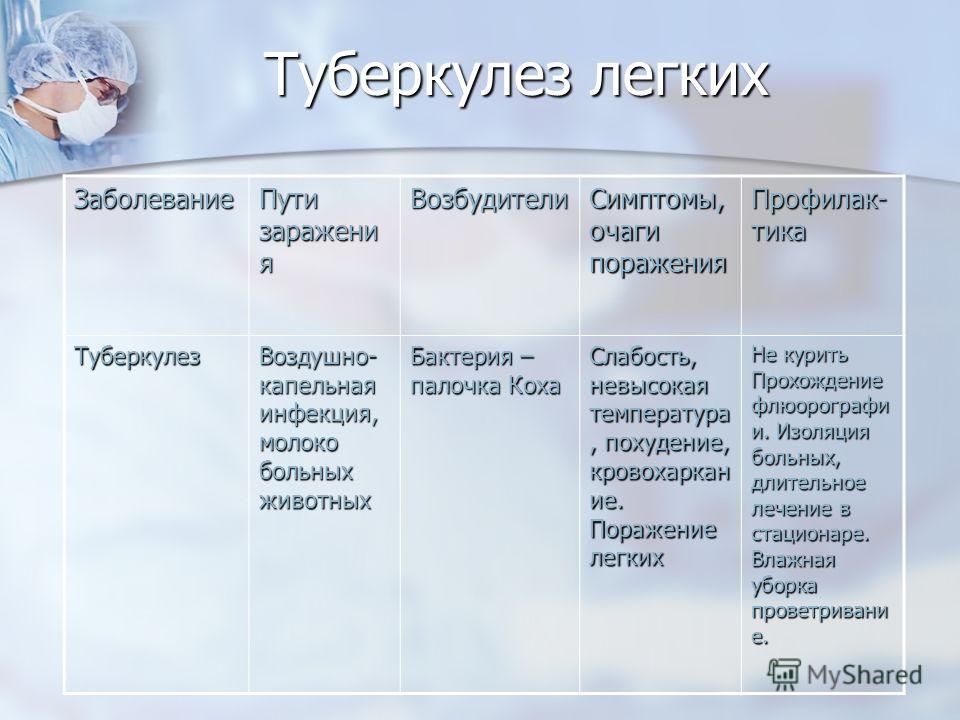

Симптомы туберкулеза: Как распознать и что делать

Раздел: Визуальные уроки